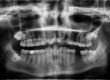

Dziś kolejny wywiad z cyklu „Kobieta ekspert”. A w nim mama trójki dzieci i lekarz stomatolog Edyta Kuza. To Ona dziś odpowie Nam na najbardziej nurtujące pytania dotyczące dzieci i stomatologii. Dlaczego właśnie ten specjalista? Bo Pani Edyta czuwa nad zdrowym uśmiechem moich dzieci i moim 🙂 Jeśli chcecie wiedzieć więcej np. Co to jest sedacja wziewna to zapraszam na wywiad!